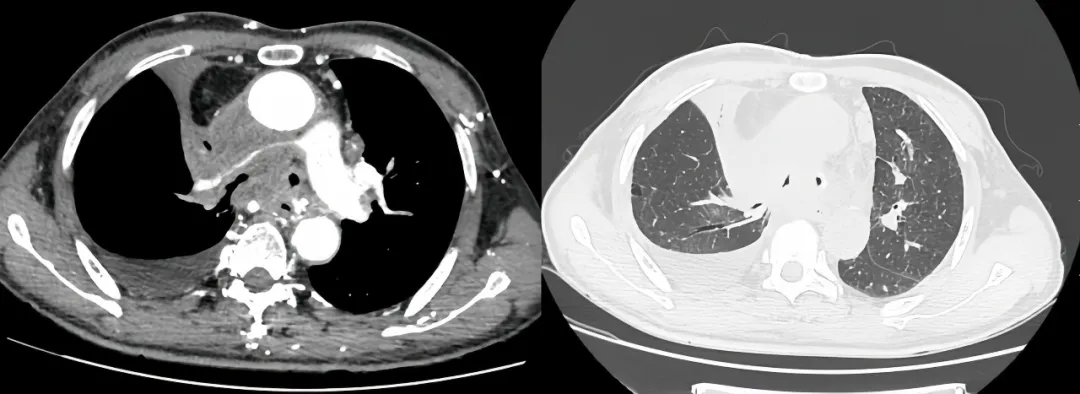

介入手术室里,一场无声的战役打响。麻醉科主任闫华凭借高超技术,成功为患者通气建立安全通路,为手术的实施奠定基石。介入科主任贺光辉带领团队细致操作,将一枚Y形气管支架在X线引导下输送至预定位置后精准释放,原本被肿瘤挤压得只剩一丝缝隙的气道被稳稳地撑开。紧接着一枚肺动脉覆膜支架置入到受压变窄的右肺动脉主干内并准确释放,再次造影,使得右肺动脉血流迅速得到改善。

同期置入支架后狭窄明显改善